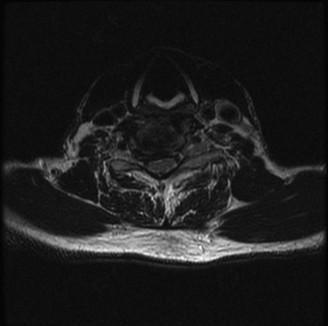

CASE 1 A 63-year-old male sustained a hyperextension injury to his neck while diving into a pool. Upon presentation, he reports decreased sensation in his hands and decreased strength in his arms and wrists, but no lower extremity complaints. On motor examination, he has 5/5 strength in his deltoids and elbow flexors and 4/5 strength in the elbow extensors, wrist extensors, and finger flexors. Lower extremity motor examination is normal. Sensation is decreased to light touch in both hands. Otherwise his sensation is preserved. Images of his cervical spine are shown in Figures 1–1 to 1–3.

Figure 1–2

The correct answer is (B). The clinical scenario describes a patient with central cord syndrome (CCS). CCS continues to be the most common incomplete spinal cord injury accounting for 15.7% to 25% of all spinal cord injuries. The characteristic presentation is an extension moment injury in a previously spondylotic and stenotic spine. Figures 1–1 to 1–3 demonstrate a spondylotic spine with central narrowing and CSF effacement that is worst at the C3–4 level. Bleeding, edema, and/or Wallerian degeneration lead to damage of the lateral corticospinal tract which is the main descending motor tract in the spinal cord. The more central anatomic position of the homunculus to the upper extremities places them at greater risk than those to the lower extremities. As such, injury to the lateral corticospinal tract is characterized by upper more than lower extremity involvement and motor deficits being more pronounced than sensory deficits.